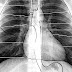

Chest radiograph By yourinfo - Desember 31, 2017 - src: lifeinthefastlane.com A chest radiograph , colloquially called a chest X-ray ( CXR ), or chest film , is a projection radiograph of th...